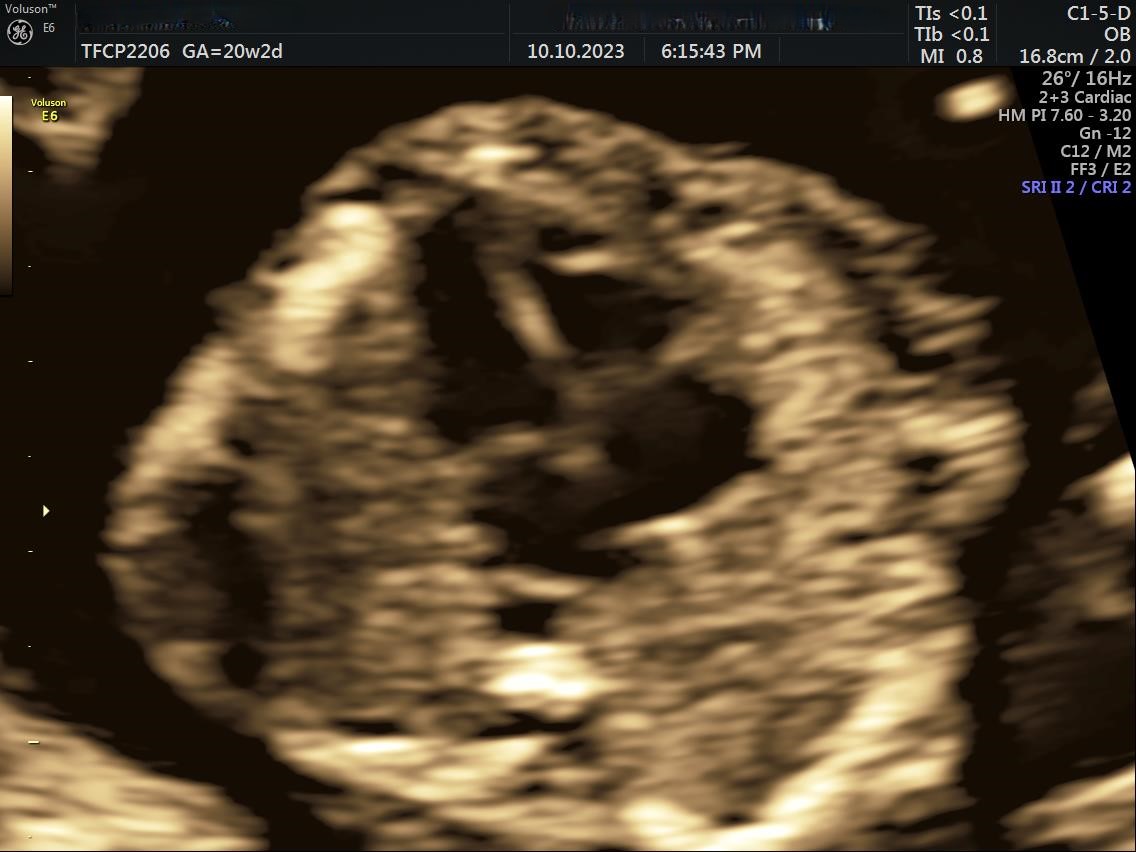

• Fetal Echocardiography(FE)

• Comprehensive mid trimester scan(TIFFA + FE + NSG)